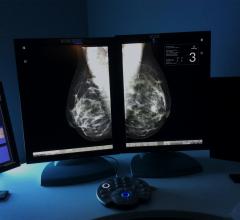

Mammography is a breast imaging technique that uses X-rays to diagnose and locate tumors of the breasts.